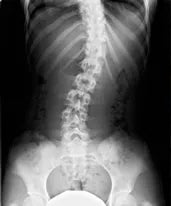

骨盤は、「 仙骨 」・「 寛骨 」・「 尾骨 」という3つの骨によってできています。

この3つの骨がバランスを取り合って骨盤という骨を形成しています。

この3つの骨が、前後左右に傾いたり、ずれてしまったり、ねじれてしまうことで「骨盤のゆがみ」になります。

骨盤を構成する骨「仙骨」「寛骨」「尾骨」

左右の骨が、前方、または後方に傾いている、またはねじれている上体です。女性に多い「反り腰」の原因にもなります。後方に倒れることを「後傾」と呼び、これは男性に多い症状です。

左右どちらかの腸骨が上がっている、または下がっている上体です。どちらかの骨の位置が上下することで左右のバランスが崩れることで、背骨そのものが大きく歪んでしまうことで、左右の足の長さが違う、肩の高さが違ってしまうことになります。

骨盤の歪みの原因として、一番多いのがこの「ねじれ」です。日常の何気ないクセ(歩くとき、座るとき、立ち上がるとき)が骨盤の「ねじれ」となって現れます。ねじれ自体が骨盤の前後のゆがみ、左右の傾きを誘発し、結果的に腰の痛み等につながっていきます。

骨盤の歪みには大きく分けて3タイプあります。